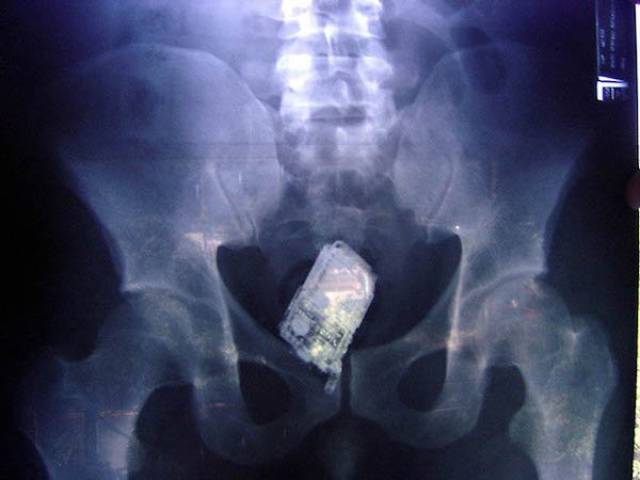

A cell phone.